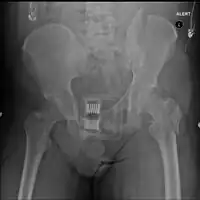

| A pelvic X-ray showing an open book fracture | |

Open book fracture

One specific kind of pelvic fracture is known as an 'open book' fracture. This is often the result from a heavy impact to the groin (pubis), a common motorcycling accident injury. In this kind of injury, the left and right halves of the pelvis are separated at front and rear, the front opening more than the rear, i.e. like an open book that falls to the ground and splits in the middle. Depending on the severity, this may require surgical reconstruction before rehabilitation.[10] Forces from an anterior or posterior direction, like head-on car accidents, usually cause external rotation of the hemipelvis, an “open-book” injury. Open fractures have increased risk of infection and hemorrhaging from vessel injury, leading to higher mortality.[11]